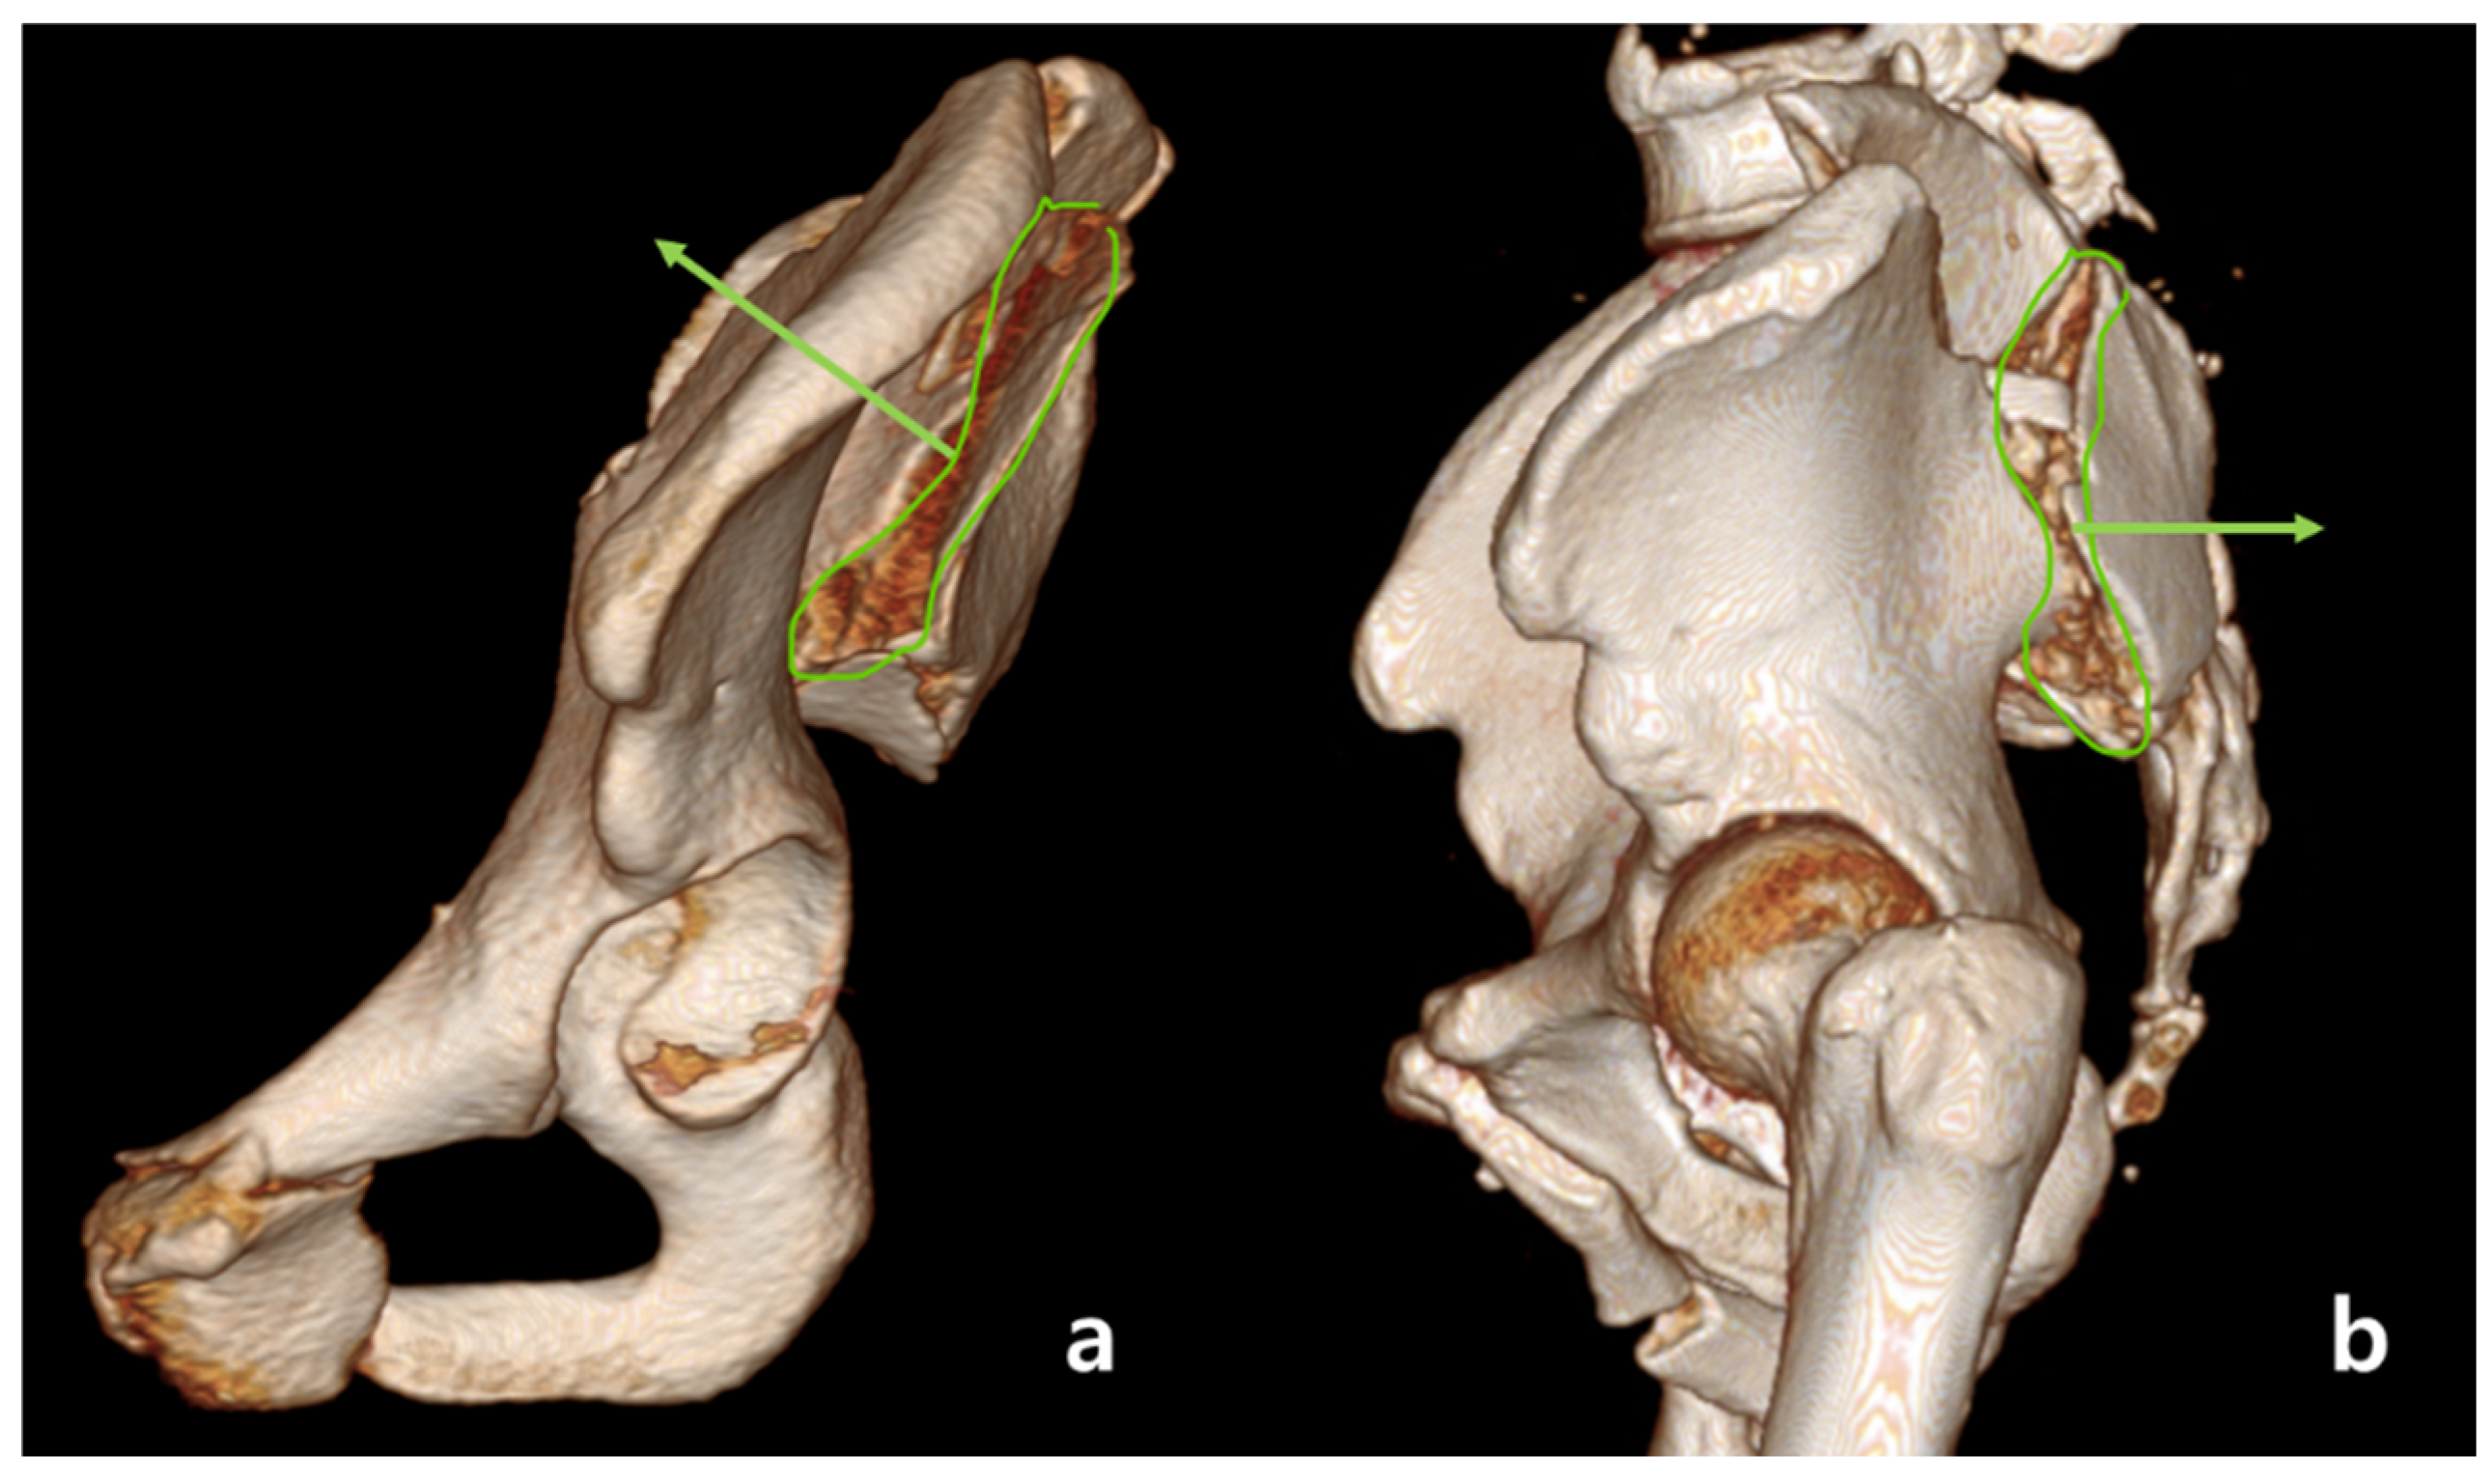

2.2. Definition of Anterior Sacroiliac Fracture Dislocation

2.3. Radiologic Assessment

2.5. Assessment of Rotational Displacement